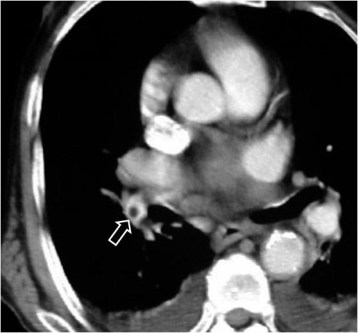

SIGNO DE FLEISHNER o DEL HILIO ABULTADO o DEL NUDILLO

En la radiografía posteroanterior o anteroposterior de tórax, la presencia de una arteria pulmonar agrandada puede indicar tromboembolismo, especialmente cuando no está presente en los estudios previos. Este signo también se llama signo de plump hilus o Signo del nudillo.

En el corte del angioTC de tórax con contraste del mismo paciente, vemos un aumento de tamaño de la arteria pulmonar, que presenta un defecto de repleción (flecha) correspondiente al tromboembolismo.

Con el mismo significado que el signo del hilio abultado se ha descrito el Signo de la salchicha o Signo de la palla. Se trata del engrosamiento de una arteria pulmonar, más fácilmente visibles en las descendentes, provocado por el trombo en el interior arterial.